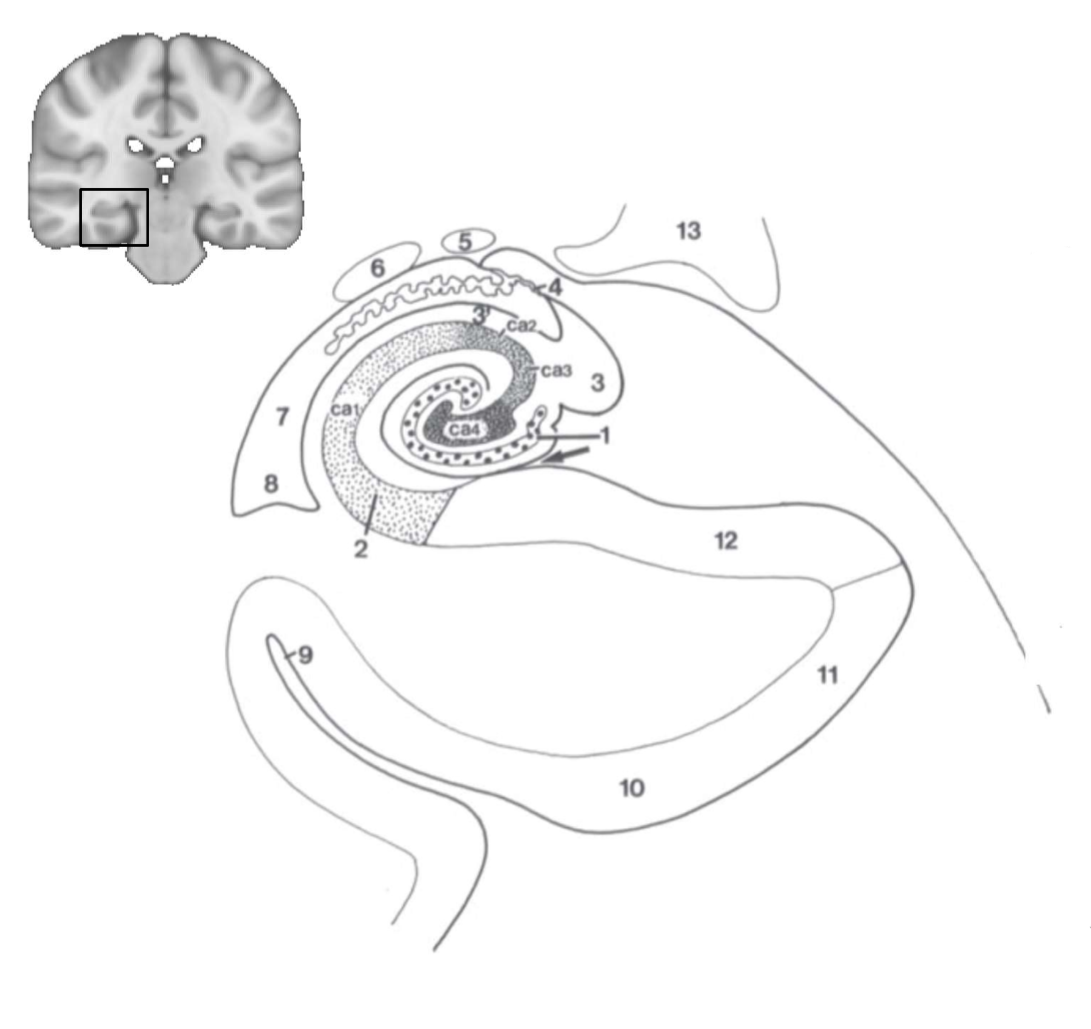

What structure is this?

hippocampus

What is 1?

hippocampus

What is 2?

rhinal sulcus

What is 3?

lateral ventricle

What is 4?

thalamus

What is 5?

entorhinal cortex

What is 6?

perirhinal cortex

What is 7?

parahippocampal cortex

What is 1?

gyrus dentatus

What is 2?

cornu ammonis

What is 3?

fimbria

What is 3’?

alveus

What is the arrow pointing to?

happicampal sulcus

What is ca1, ca2, ca3 and ca4?

fields of cornu ammonis

What is 4?

tela choroidea

What is 5?

stria terminalis

What is 6?

tail of caudate nucleus

What is 7?

temporal horn of lateral ventricle

What is 8?

collateral eminence

What is 9?

collateral sulcus

What is 10?

parahippocampal

What is 11?

entorhinal area

What is 12?

subiculum

What is 13?

lateral geniculate body